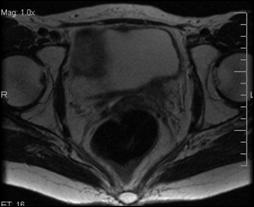

b). Neoplasm de col uterin, invaziv in vezica urinara

a. b.

a) Tumora de col uterin, invaziva in vezica urinara - pacienta s-a prezentat in anurie; b) Tumora de col uterin, operata (histerectomie totala + iradiere), recidivata, invadand vezica urinara si rectul - pacienta s-a prezentat cu hematurie